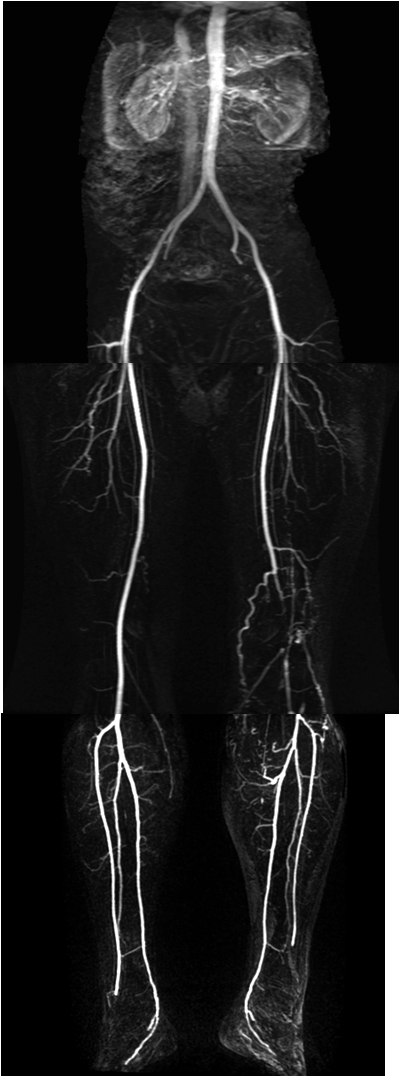

Image

Contrast enhanced MR angiography"

Fig. 22. Left sided segmental occlusion at the iliofemoral segment

CT angiography

Fig. 23. Bilateral superficial femoral artery occlusion with collateral filling

Multi-slice CT is able to perform CT angiography scans that map the body from the diaphragm to the ankles depicting the complete arterial tree with adequate intensity and with appropriate spatial resolution. In most cases this has a sufficing diagnostic value and it is especially advantageous for the rapid assessment of patients in poor condition. For the MRA of this wide region a special table toggling technique is required. This method applies prolonged injection of intravenous bolus contrast medium, and in three table-toggling steps it can visualize the arterial system of the abdominal aorta and the peripheral arteries up to the ankle with an acceptable spatial resolution. MRA examinations has the best diagnostic value for lesions presenting at the aortoiliac and femoropopliteal regions in cases with a relatively limited extension and a reasonable severity. CTA examination (with specific contrast injection protocol) provides better spatial resolution tough even in this region starting to replace angiography as a first choice of examination in the diagnostics of acute coronary syndromes.